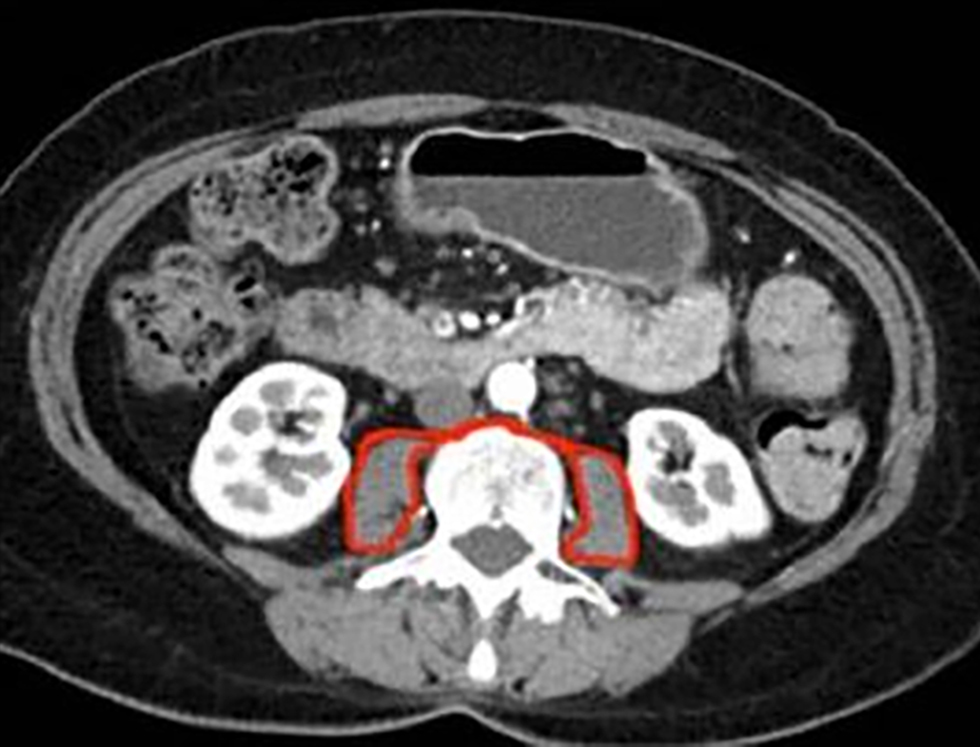

Figure 1 - Total psoas area (TPA) at the level of L3 with both vertebral spines visible

The total cross-sectional area of the psoas muscles (total psoas area, TPA) was assessed employing a manual technique at the level of the L3 vertebra during the preoperative CT scan (17). To confirm standardization, the precise level of assessment was determined as the CT slice in which both L3 transverse processes were most clearly visible. The area was delineated with a free-hand drawing method on Picture Archiving and Communication System (PACS) software (fig. 1). The contour of each psoas muscle was delineated. The area of each was calculated and summated to provide the TPA (mm2). The TPA was then standardized for patient height using the formula: TPA (mm2)/height (m2). This provided the total psoas index (TPI) for each patient.